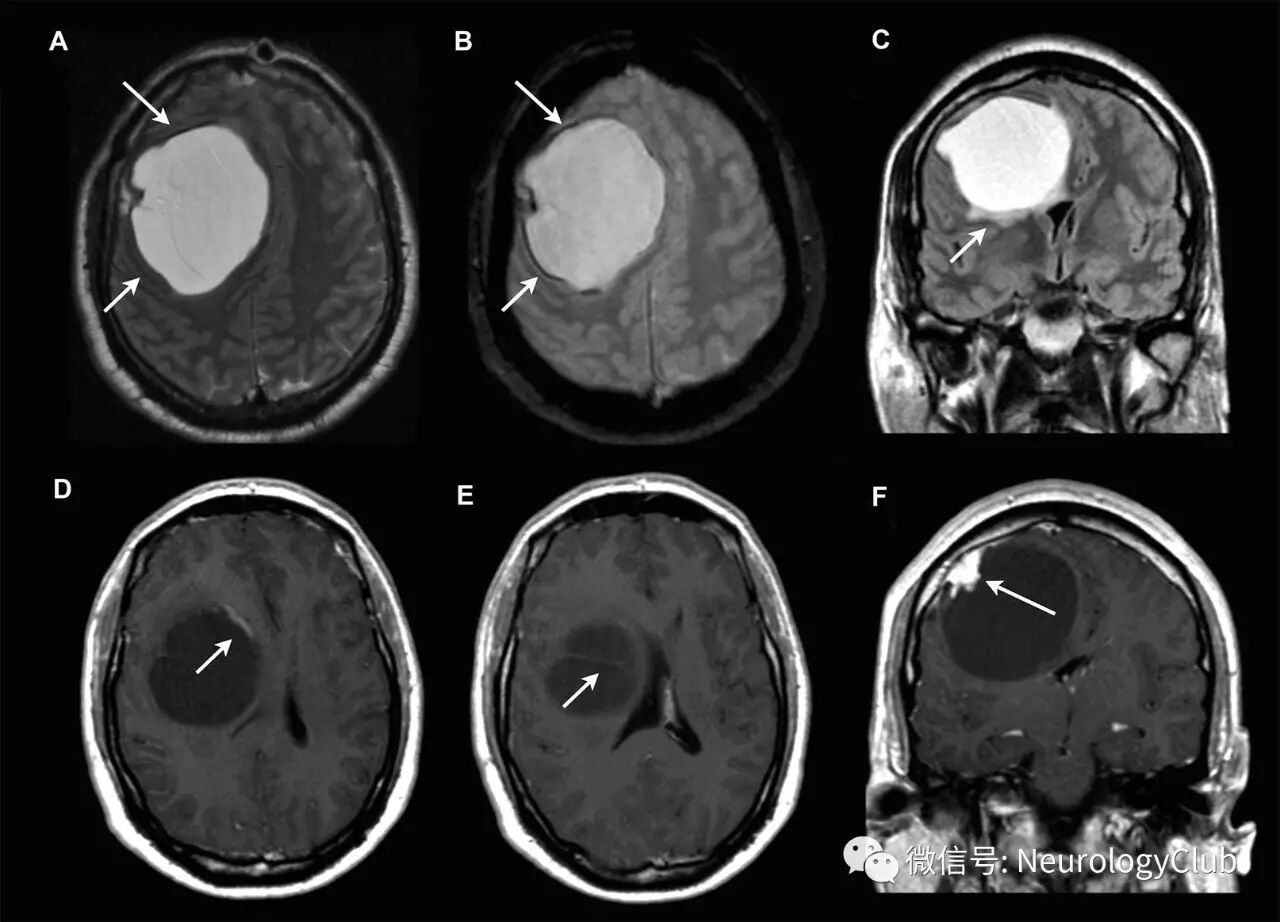

40岁男性,表现为进行性左半身无力和头痛。几个月前还出现了行为改变。未见颅神经功能障碍。T2WI上可见右额叶囊性肿块,伴周围出血或钙化(图A-B,箭)。无法区分病灶位于脑内还是脑外。FLAIR上可见病灶周围水肿(图C,箭)。T1增强可见囊壁线样强化(图D,箭),瘤内分隔(图E,箭)和强化附壁结节(图F,箭)。

(图:MRI可见右额叶囊性病灶;A-B:T2WI;C:FLAIR;D-F:T1增强)